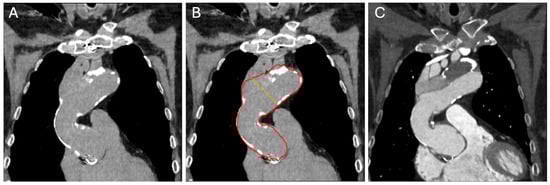

The aortic diameter measurements were performed using a combination of multiple DNN models (Figure 1). An image-to-image U-Net segmentation model was first used to segment the aortic region (Figure 2). Then, a deep reinforcement-learning-based landmark model was used to detect landmarks corresponding to the aortic root, brachiocephalic artery, left common carotid artery, left subclavian artery and celiac artery. These landmarks and the aortic segmentation were used to compute the aortic centerline, along with a local coordinate system denoting the normal and in-plane directions (defining the cross-sectional plane) to the centerline at each point. The length of the aortic centerline was then partitioned into regions corresponding to the ascending, aortic arch and descending sections of the aorta, and the maximum average diameters in the ascending and descending diameter are given as outputs.

Figure 1. Steps involved in quantifying diameters at the widest location in each section of the aorta. (A) Candy-cane view of a thoracic aorta with a dissection in contrast-enhanced CT. (B) Probability map of the AI prediction model of the aorta. The red color shows the highest confidence for the model. Yellow, green and blue each represent a decreasing level of confidence, respectively, with red indicating the highest confidence. (C) An inclusion cutoff for the confidence level is picked, and the segmentation of the aorta can be generated based on this selection. (D) From this segmentation, the maximum diameters in each section may be calculated. AI = artificial intelligence; CT = computed tomography.